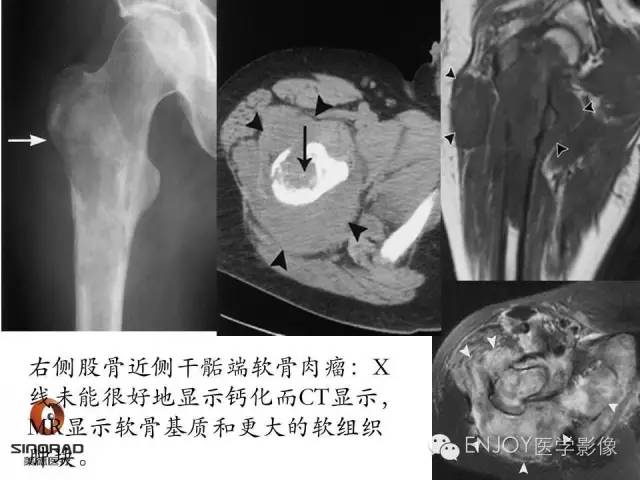

多形性肉瘤(以往称为:恶性纤维组织细胞瘤)

软骨肉瘤(2-3级)